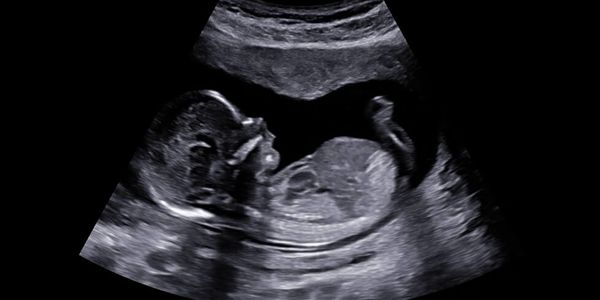

Ultrasound has been used in pregnancy care for decades and is considered safe when performed properly. Unlike X-rays, ultrasound does not use radiation. Instead, it uses sound waves to create images of your baby. The FDA, ACOG (American College of Obstetricians and Gynecologists), and many studies have found no confirmed risks to mothers or babies when an ultrasound is used responsibly to industry and machine guidelines. We take great care to ensure that we only use settings that are appropriate for the stage of pregnancy you are in.

We offer elective, non-medical ultrasound sessions designed to bring you closer to your baby before birth. From clear 2D imaging to breathtaking 3D/4D ultrasounds, our services are built to showcase every tiny detail — from wiggles and yawns to smiles and stretches. We also offer cozy bonding sessions where you can share the experience with loved ones in a welcoming, family-friendly setting. Each service is thoughtfully crafted to give you not just a glimpse, but an unforgettable memory of your baby’s earliest moments.